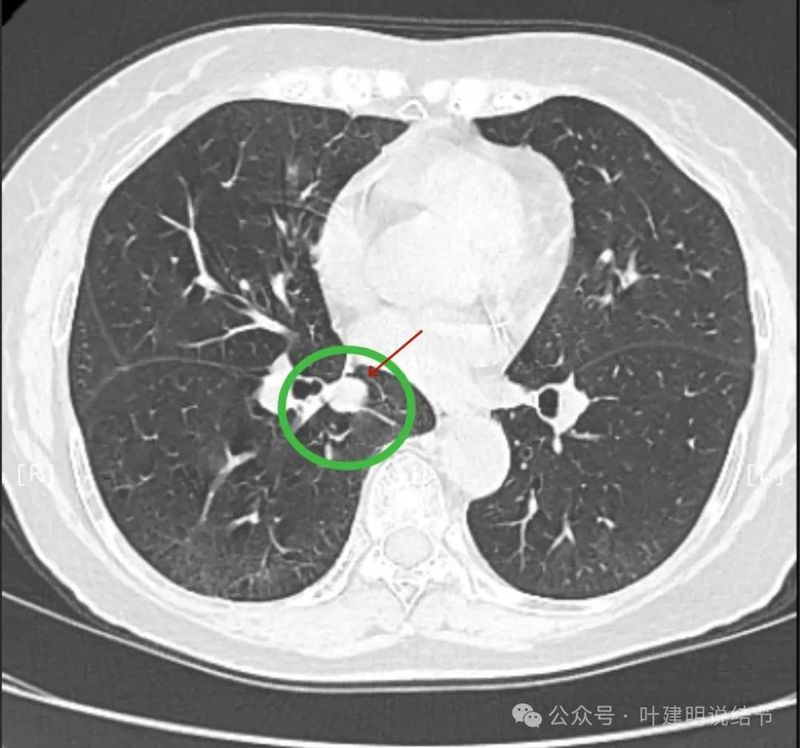

再看2024年5月时复查的影像:

分叶,混合偏实性密度,血管贴边走行。

与支气管紧贴,黄色箭头所示处似乎支气管壁与病灶已经愈着。

上图又见结节与支气管不是都愈着的,说明侵袭性并不强,病灶表面光滑。

天蓝色箭头所指处是北段支气管与病灶之间,感觉较2月份贴得近了一点点。病灶表面仍是光滑的,总体感觉有膨胀性。

病灶边缘光滑,有血管穿出来似的。

表面光滑,有膨胀性。

内部密度较为均匀,就位于肺门部。

边缘光滑,实性,有膨胀感。

与血管关系近。

边缘区域与下肺静脉间隙不太清楚。